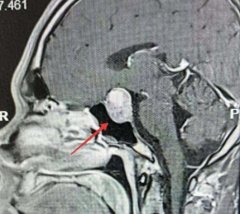

垂体瘤

• 40岁男子鞋越穿越挤、声音变浑厚,竟是颅内藏“元凶”

医生 垂体腺瘤 垂体瘤 2026/04/26